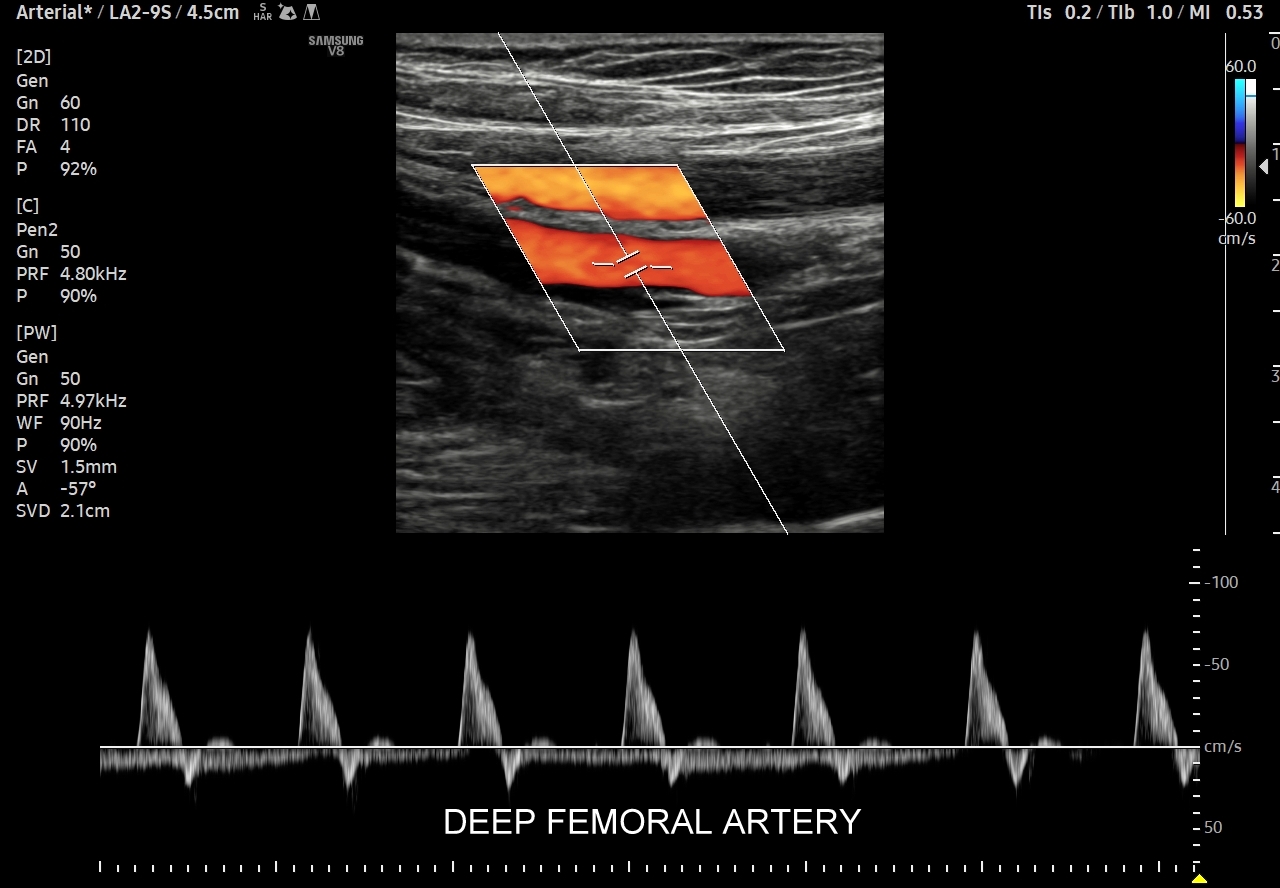

- Z kolei profile o wysokiej pulsacyjności charakteryzują się tym, iż posiadają wąskie i ostre piki skurczowe, a w fazie rozkurczowej odwrócone lub/i nieobecne przepływy. Profile tego typu występują w tętnicach unaczyniających kończyny.

W przypadku tętnic podążających do kończyn w warunkach spoczynkowych obserwuje się charakterystyczne wielozałamkowe profile przepływów zawierające od 2 do nawet 4 następujących po sobie przeciwstawnych załamków o zmniejszającej się amplitudzie, przy czym w tętnicach tych zwykle nie obserwuje się ciągłego przepływu w fazie rozkurczowej. Stały lub prawie stały przepływ rozkurczowy, tj. przepływ o pośredniej pulsacyjności, może pojawić się w tętnicach kończyn w trakcie intensywnego wysiłku fizycznego.